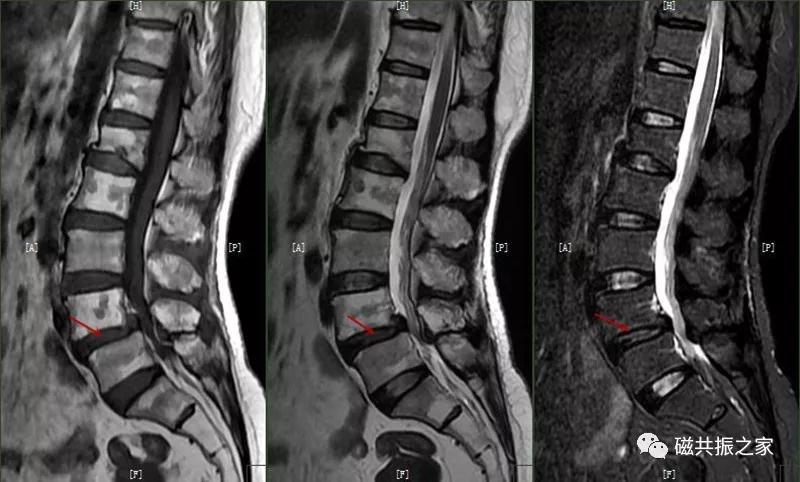

8.椎体骨折

椎体压缩性骨折常成前窄后宽的楔形改变,新鲜骨折(红箭头)常在T1WI呈低信号(出血时可呈高信号),T2WI呈低、中信号,在脂肪抑制的T2WI上呈高信号。椎体陈旧性骨折(白箭头)信号类似于正常椎体信号。如需了解脊柱骨折分型请查阅脊柱骨折的分型。